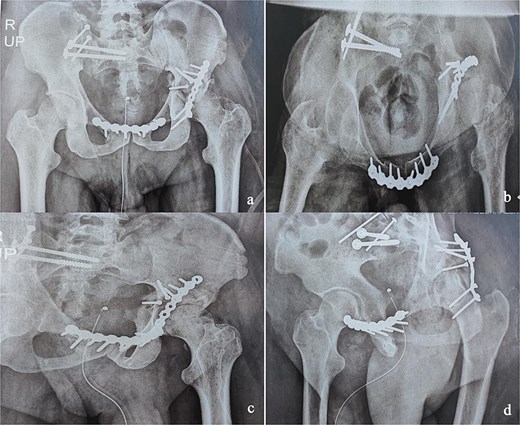

At the 10-month follow-up, the patient showed signs of left hip osteoarthritis with functional deterioration, for which a total ceramic-on-ceramic hip arthroplasty was performed, using a screw-fixed structural graft at the acetabulum (Fig. 3). At the final follow-up, 36 months postoperatively, the patient was walking unaided with the use of an anti-equinus splint on the left foot. The HHS was 85 and Majeed score was 86 [6, 7]. X-rays showed complete bone healing of all fractures and the acetabular graft. It should be noted that, during follow-up, the patient had a right femoral fracture that was successfully treated with a gamma nail (Fig. 4). Written informed consent were obtained from the patient.